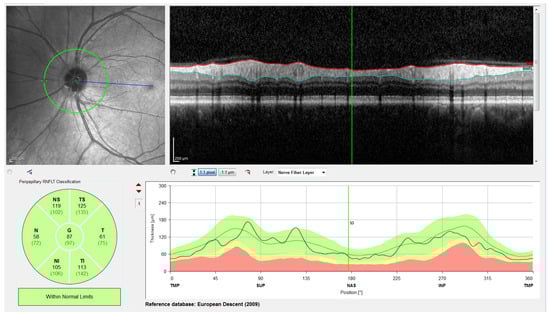

Note that this cylindrical section is projected from polar to Cartesian coordinates for easier processing and analysis. This projection together with its corresponding x- and z-scaling is displayed in the top right of Figure 2. The correspondence between the sectors of the analysis circumference and the x-coordinate of the peripapillary OCT images is gathered in Table 2 and illustrated in Figure 3.

Figure 2.

Screenshot provided by the Spectralis software version 6.9.4.0. From left to right and top to bottom: Retinal fundus photography centered on the optic disc (the yellow circle indicates the location of the peripapillary B-scan, which is shown on the right with the segmentation of the RNFL); 2D peripapillary B-scan OCT on Cartesian coordinates; estimated mean values for RNFL layer thickness for the temporal (T), temporal superior (TS), nasal superior (NS), nasal (N), nasal inferior (NI), and temporal inferior (TI) sectors, as well as the overall mean (G); rectified outline of the RNFL with estimated thickness and reference values according to the database European Descent (2009).

The OCT images used in this work have a resolution of 768 × 496 pixels with a z-scaling of 3.87 µm/pixel and a bit depth of 8 bits/pixel in grayscale. The diameter of the peripapillary OCT circumference can be adjusted according to the size of the patient’s eye, varying the horizontal resolution of the OCT accordingly. For instance, a circumference diameter of 3.7 mm corresponds to a x-scaling of 15.21 µm/pixel. Note that only the z-scaling was used for this work, since the main goal is to determine the vertical thickness of the RNFL in the OCT image. The top left of Figure 2 shows the circular tracing of the SLD beam on the retinal fundus image of the eye. This analysis circumference is positioned over the center of the optic nerve (or papilla) as depicted in the figure.